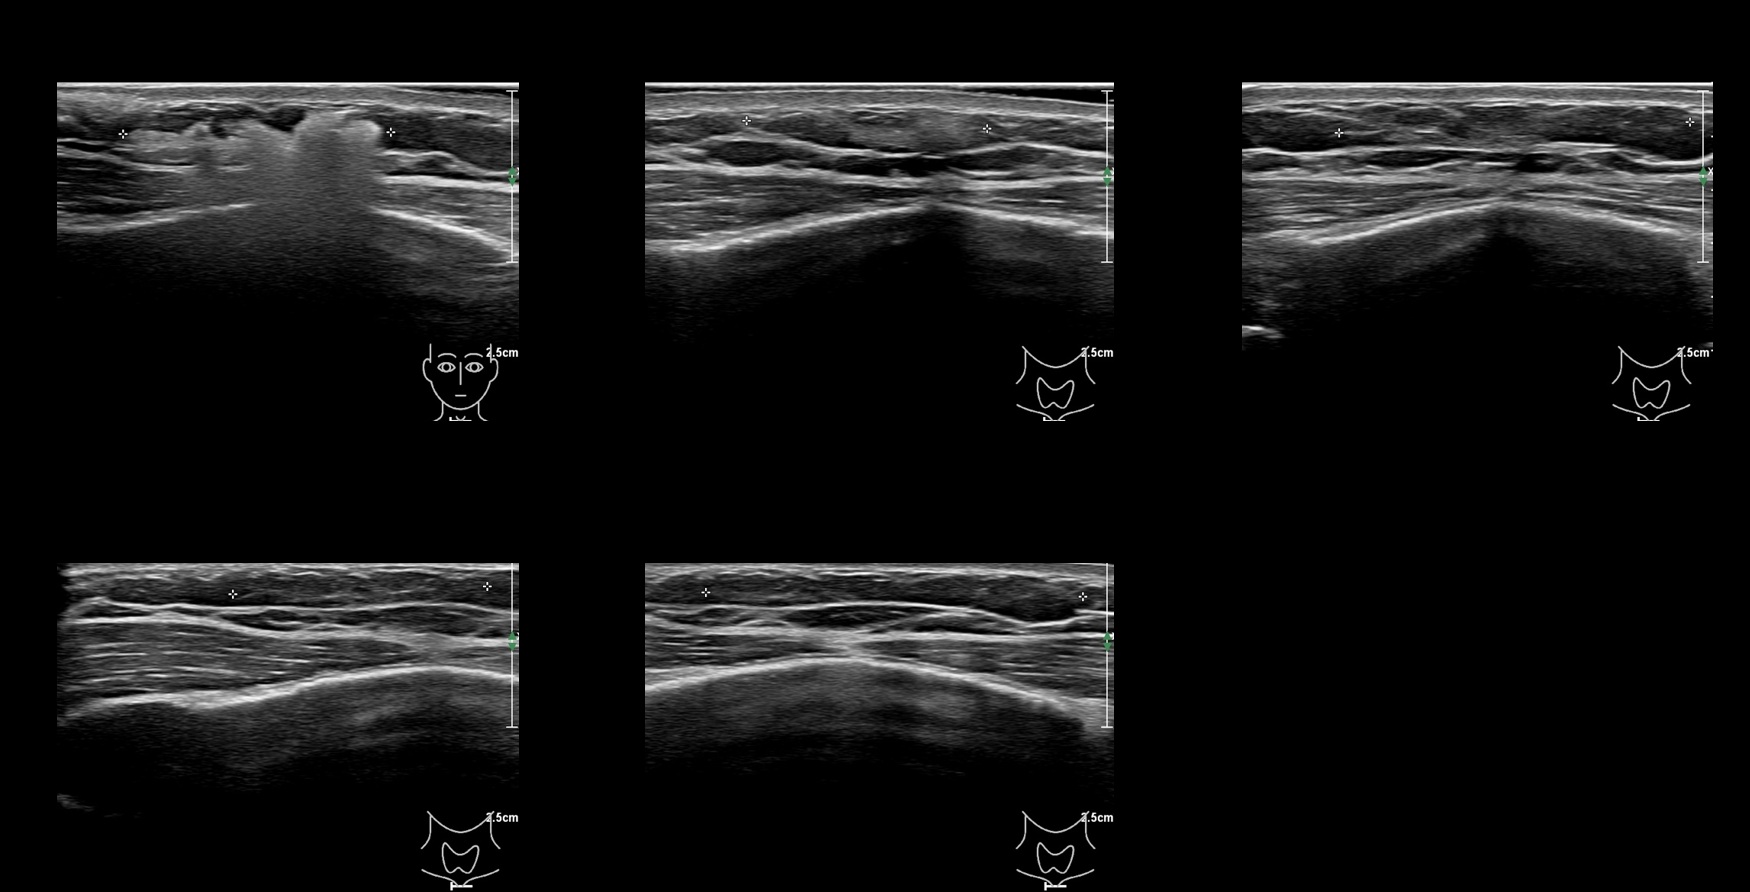

Draw in the image on the right where the fillers are located. To check if your answer is correct, please click on the secondary image.

Draw in the second image below where the fillers are located. To check if your answer is correct, swipe the first image to the right.